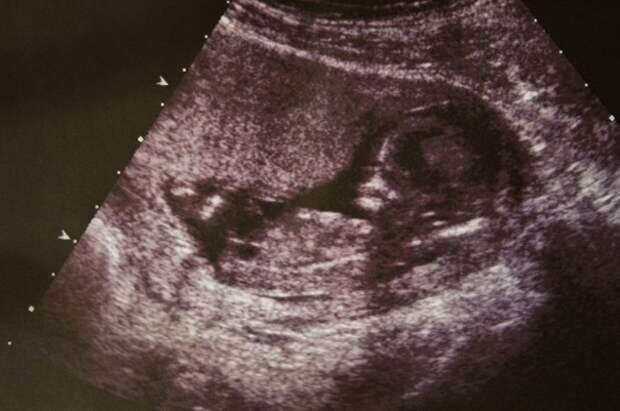

Когда врачи сделали кесарево сечение, увидев малыша, они не поверили собственным глазам.